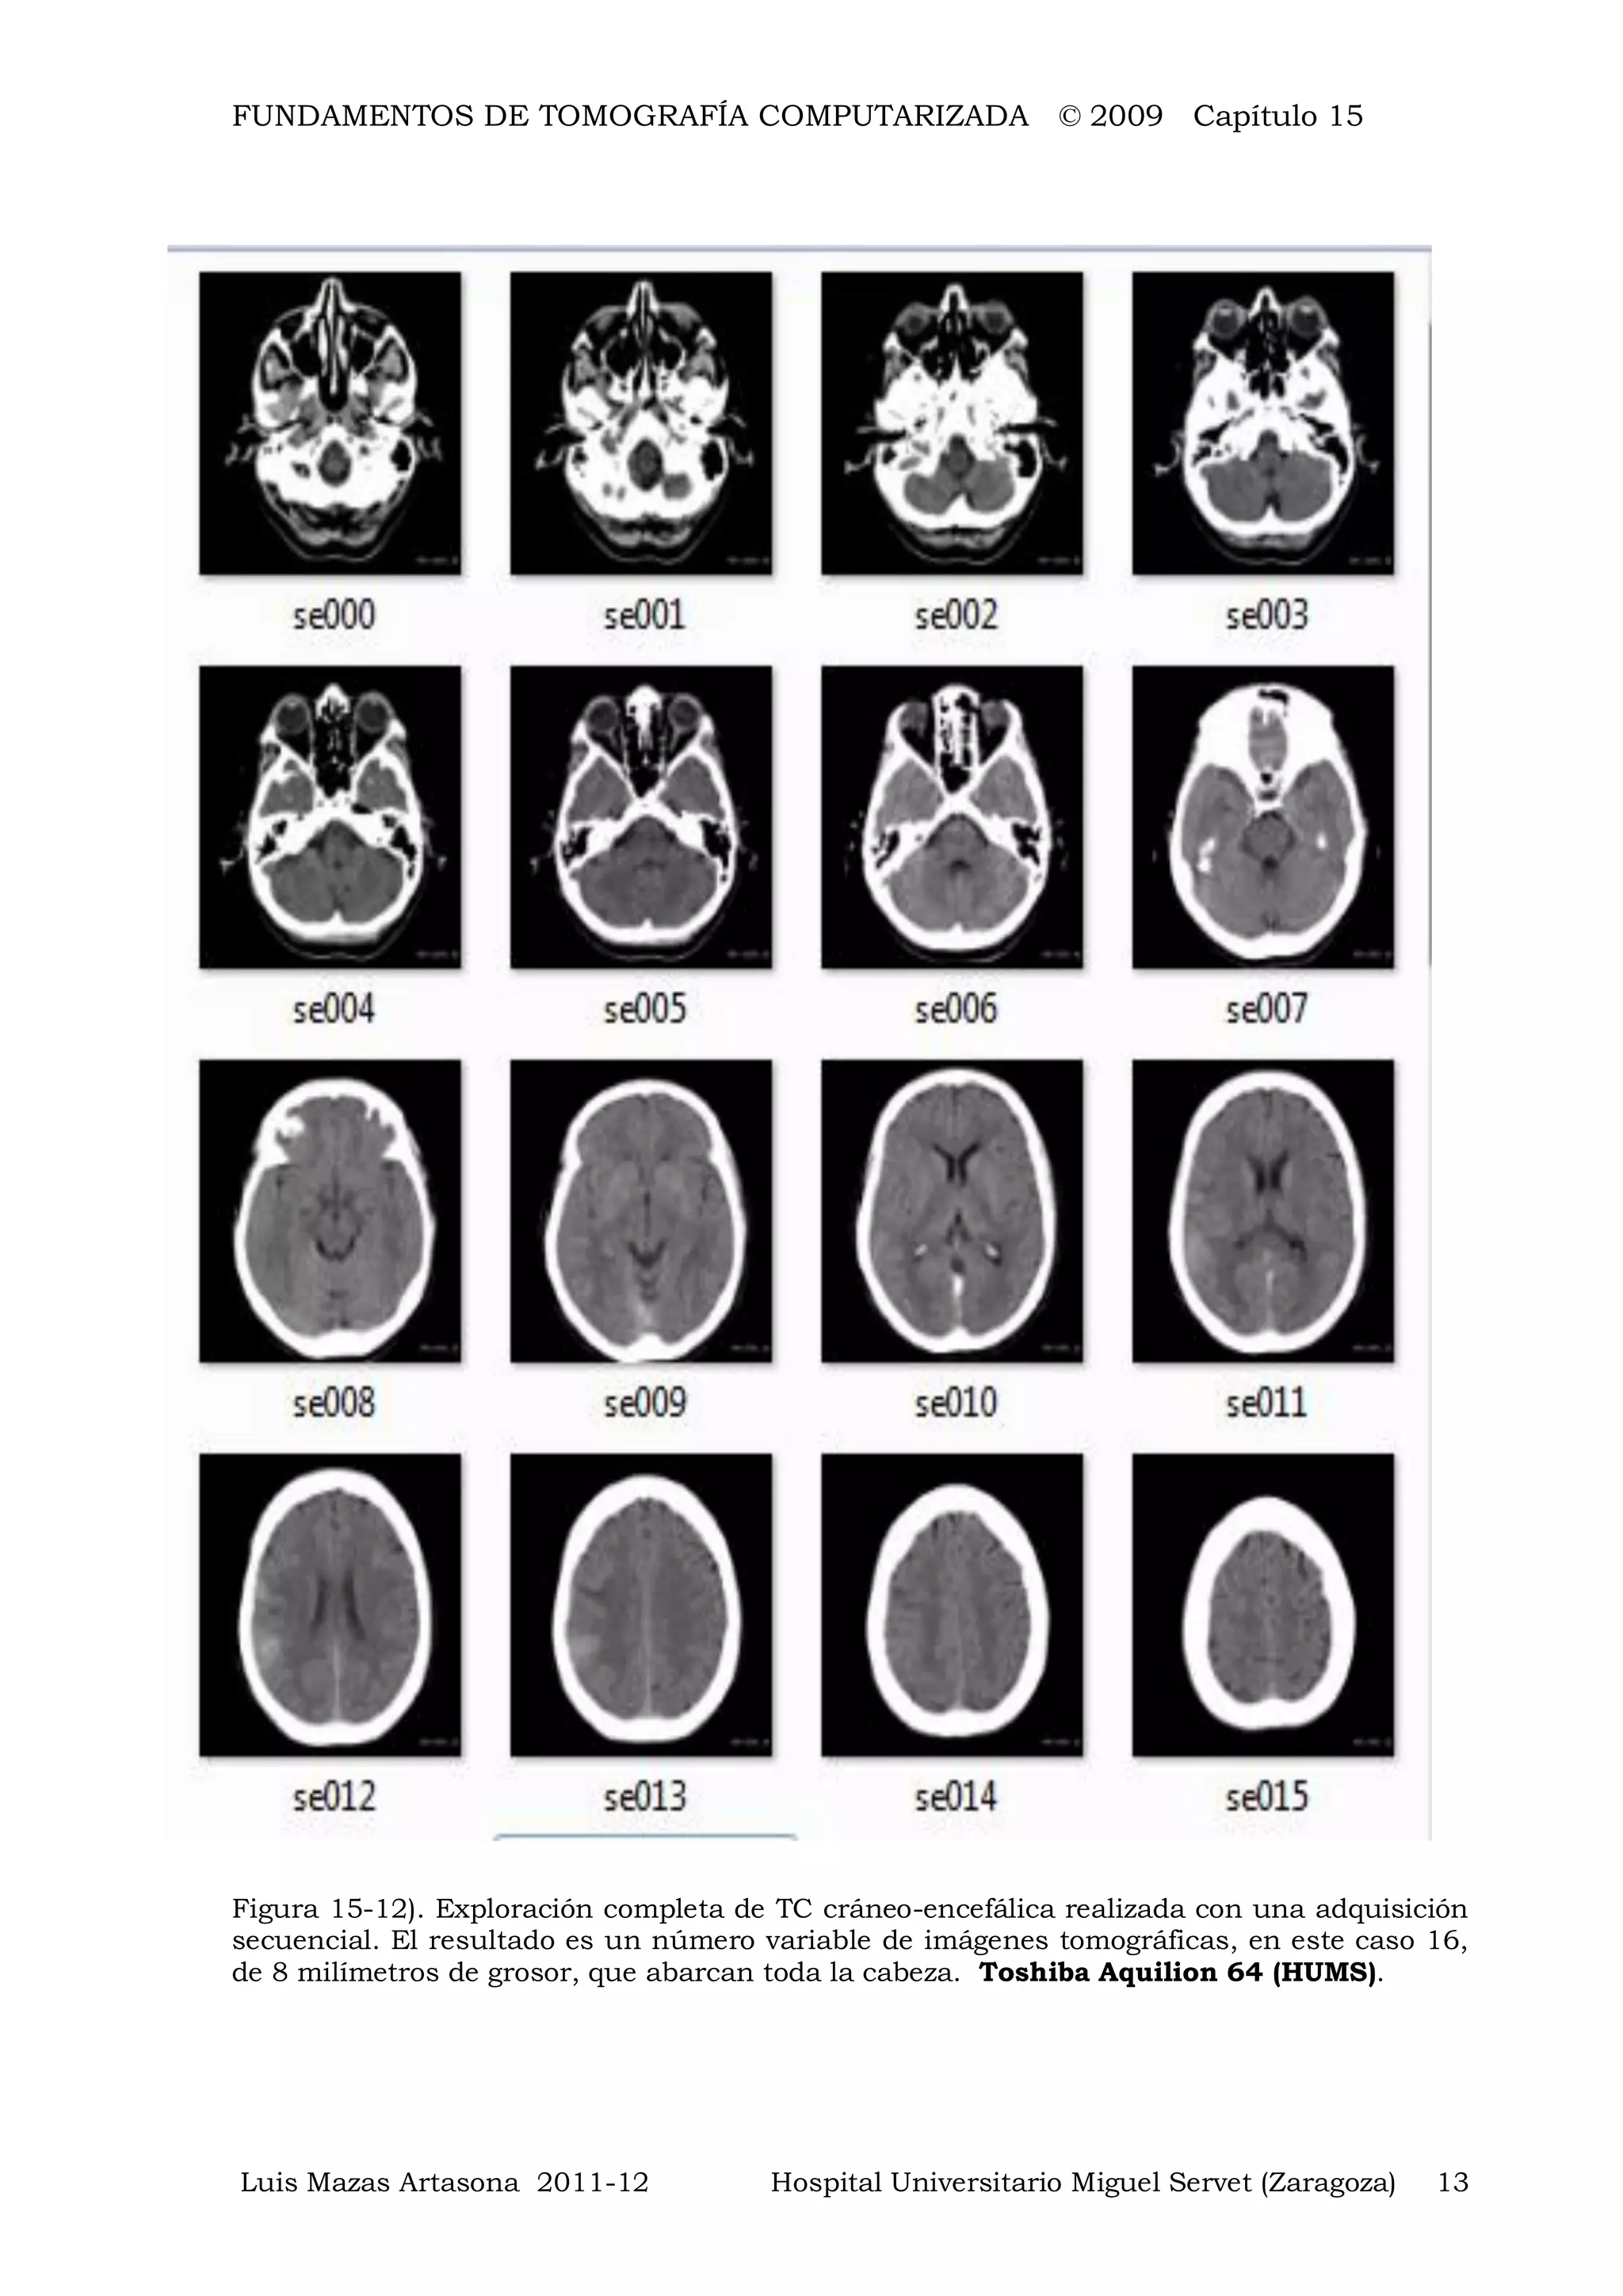

Figura 15-12). Exploración completa de TC cráneo-encefálica realizada con una adquisición

secuencial. El resultado es un número variable de imágenes tomográficas, en este caso 16,

de 8 milímetros de grosor, que abarcan toda la cabeza. Toshiba Aquilion 64 (HUMS).